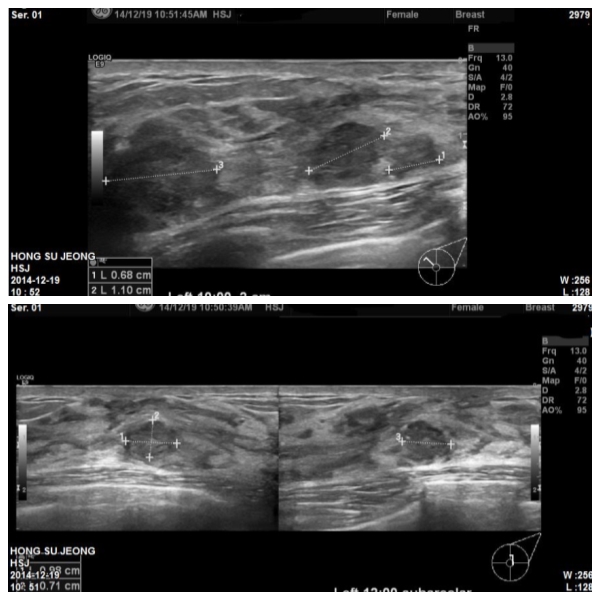

좌측유방에 만져지는 멍우리로 내원하신 47세 환자분이십니다

유방초음파 시행 후 좌측 10시방향에 1.4cm 와

12시방향 유륜아래에 0.9cm 의 혹을 조직검사하였고 결과상 두혹모두

침윤성유방암으로 진단되었습니다.